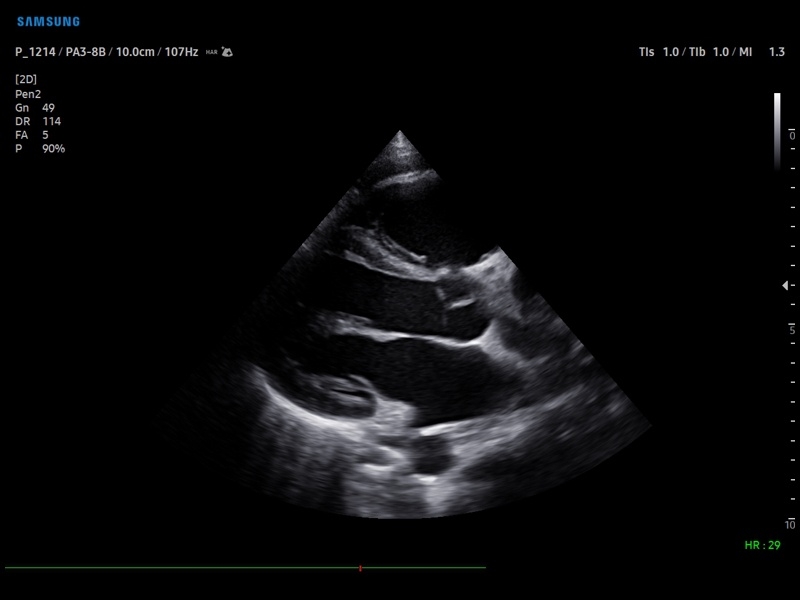

• Кардиология

Кардиология:

• M - одномерный режим для исследования сердца, анатомический М-режим (необходим кардиопакет), CM - цветной М-режим (необходим кардиопакет).

• Кардиопакет: тканевый допплер (TDI) + анатомический М-режим + цветной М-режим (CM) + программное обеспечение.

• Пакет кардиологических исследований.